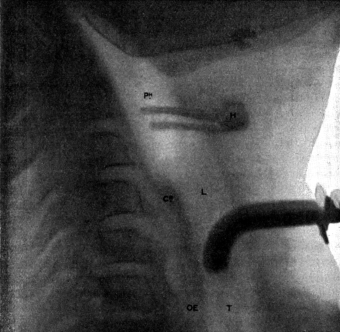

| 267. | Skiagram showing an Angular Tracheotomy Tube in the Trachea | 518 |

| 268. | Anatomy of the Larynx and Trachea and the Position of Incisions for the Operations in this Region | 525 |